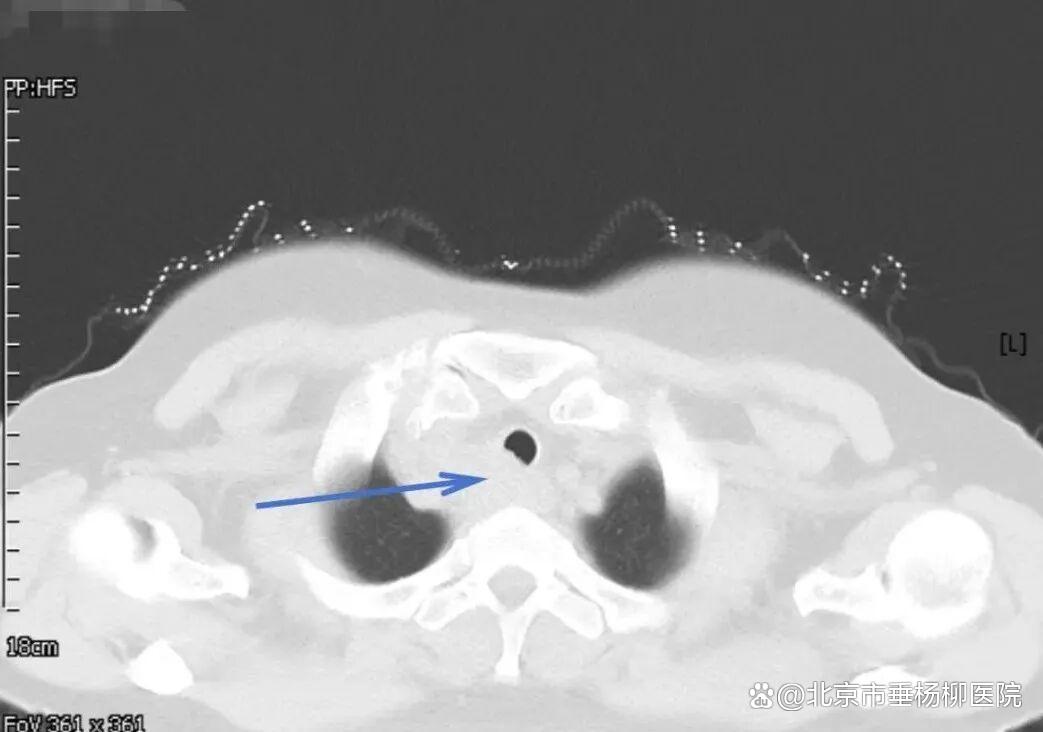

经过胸外科团队的成功采样,医院病理科专家当晚即对穿刺标本进行分析,镜下可见真菌菌丝,形态符合曲霉菌感染,未见恶性肿瘤细胞。“不是癌,是感染!”这个结果让所有人松了一口气。医疗团队随即为患者制定抗真菌治疗方案,经系统治疗后,患者吞咽哽咽感明显缓解,复查影像显示病灶显著缩小。

▲治疗后一个月胸部CT